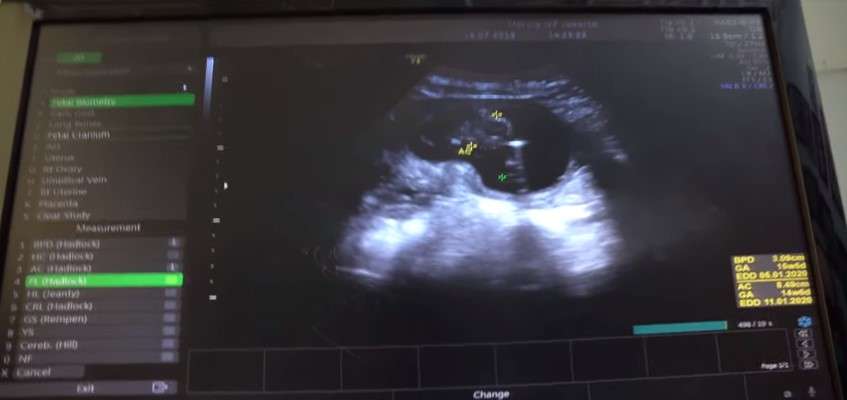

Melalui video itu juga, Rifky dan Biby memperlihatkan proses pengecekan kandungan yang sudah berusia empat bulan. Rifky pun meminta doa kepada warganet.

" Jadi kita sekarang mau kontrol udah mau masuk hampir empat bulan jadi doain sehat-sehat terus. Setiap ahri juga Baby juga tidak boleh capek dan jaga makanan," tambah Rifky.